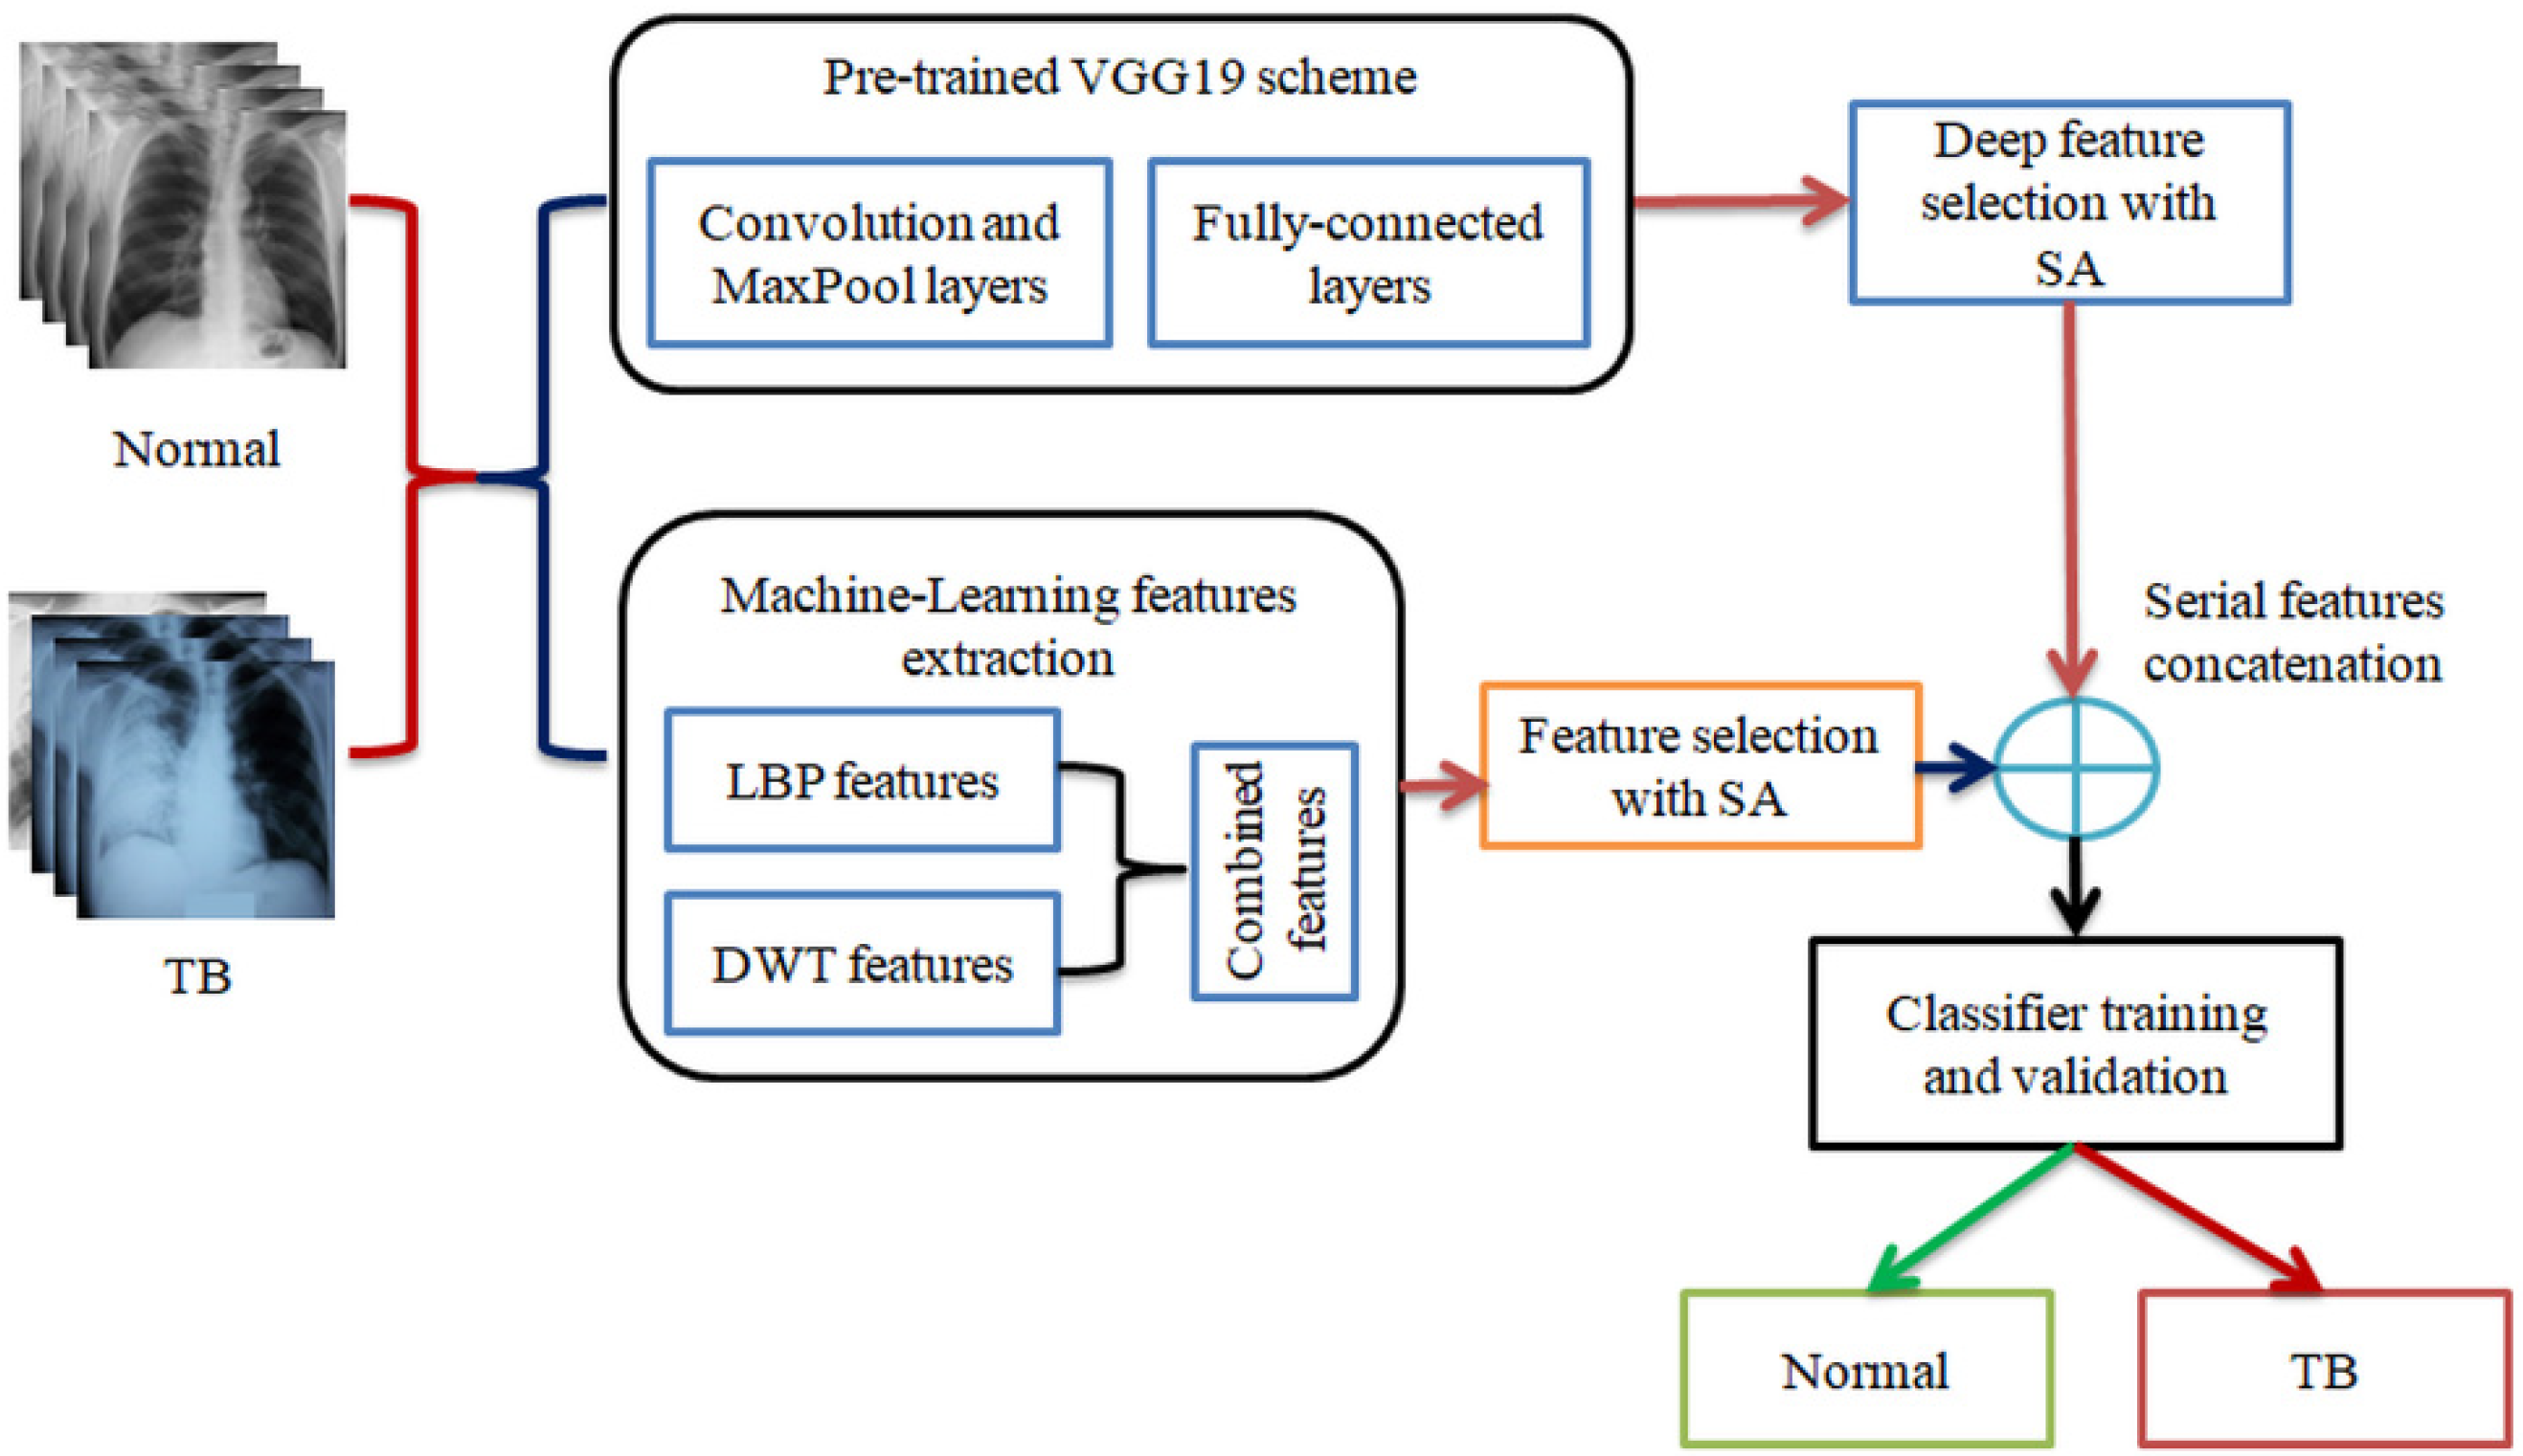

- (i)

- Implementation of pre-trained DLS-based TB detection from chest X-ray;

- Generation of MLF using LBP and DWT;

- SA-based feature optimization and serial feature concatenation to obtain DLF+MLF.

3. Methodology

3.2. Pre-Trained VGG19

3.3. Feature Extraction

3.3.1. Deep-Learning-Features

3.3.2. Machine-Learning-Features

3.4. Seagull-Algorithm Based Feature Optimization